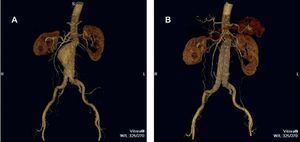

Endovascular treatment has been increasingly employed since the initial clinical experiences of Parodi in 1991.46 Aneurysm exclusion is achieved by means of endograft implantation. With the consolidation of endovascular treatment, the degree of complexity of the aneurysms treated has increased because of the versatility of the endograft, making it possible to place aortouniiliac grafts, bifurcated grafts, grafts with suprarenal fixation and fenestrated grafts, or use hybrid techniques in which aneurysm exclusion is combined with surgical visceral revascularization. Although this approach was initially indicated only in those patients in whom conventional surgery was highly risky, there are many groups that advocate endovascular AAA repair (EVAR) as the first option. When the anatomy is favorable, the advantages are significant: a high rate of technical success (96% to 100%), avoidance of laparotomy, bowel manipulation and aortic clamping, a lower incidence of postoperative ileus and need for transfusion, better control of postoperative pain and shorter intensive care unit and overall hospital stays.47 Above all, the rate of perioperative mortality is lower, as has been demonstrated in recent prospective, randomized trials involving patients at low surgical risk.48-50 The reduced invasiveness has made its application in aneurysm rupture possible, with promising results.51

The purpose of EVAR is to provoke the thrombosis of the excluded sac, the reduction of the aneurysm diameter and, finally, the elimination of the risk of rupture (Figure 3). However, specific complications (leaks, migration, material fatigue, graft occlusion, infection) (Table 1) require indefinite patient follow-up and are frequently the cause of reinterventions. It is precisely the reinterventions, mostly involving endovascular procedures associated with a low mortality rate, that limit the widespread use of EVAR. However, future technological developments will minimize this drawback.52,53

Figure 3. Image of an abdominal aortic aneurysm obtained by computed tomography angiography with 3-dimensional reconstruction (A). The results of exclusion by means of endoprosthesis implantation can be observed (B).